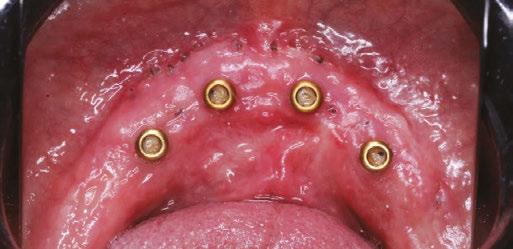

Figures 9A-9I: Management of ANS greenstick fracture via horizontal ridge augmentation. 9A. Pre-op. 9B: Stabilization of ANS greenstick fracture via “sausage”-based technique using two 20x30 RCMs and 4-0 PGCL sutures. Membrane-stabilizing sutures used: periosteal vertical mattress suture (PVMS) at lateral-most extent of the graft area. PVMS at the medial extent of each membrane (another PVMS was added just left of midline after photo was taken). Apical periosteal and palatal membrane tacking sutures. 2.5cc particulate 80/20 FDBA (corticocancellous)/xenograft (porcine) was used. 9C. 6-month post-op. Patient allowed limited wear of denture (shortened flange in anterior) 2 months post-op. 9D. Uncovering with view of the repaired ANS with regenerated bone. Implant placed in NP canal @ 25 Ncm. 9E. Occlusal view. 9F. L-PRF prepared (700 RCF, 8 minutes) and placed all along arch to aid in soft tissue healing. Flaps intentionally sutured to allow healing by secondary intention to increase KT. Conversion prosthesis loaded, patient educated about anterior cantilever. 9G. 1-week follow up. The power of L-PRF. 9H. 3-month follow up. 9I. Uncover at 3 months post placement of NP implant. 9J. CBCT Axial View. AP spread with (14.4 mm) and without (9.3 mm) NP implant